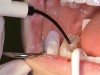

For this case, a light-cured sealant was used (Figure 7). In order to light cure the sealant, there must be sufficient energy to harden the resin sealant. The light must be providing at least 600 mW/cm2 from its tip; the tip of the light must be free of cured resin and not be broken to make sure that sufficient energy is light curing the sealant. It is critical that the curing light be placed within 1 mm of the tooth’s occlusal surface, at right angles to the tooth, and the sealant be cured at least 10 seconds. The light probe must cover the entire occlusal surface. If the diameter of the light probe is too narrow, light cure the mesial first for 10 seconds and the distal for an additional 10 seconds. The sealant is then evaluated for retention and seal of the occlusal surfaces (Figure 8).

Figure 7  Light curing the sealant for 10 seconds

Figure 7